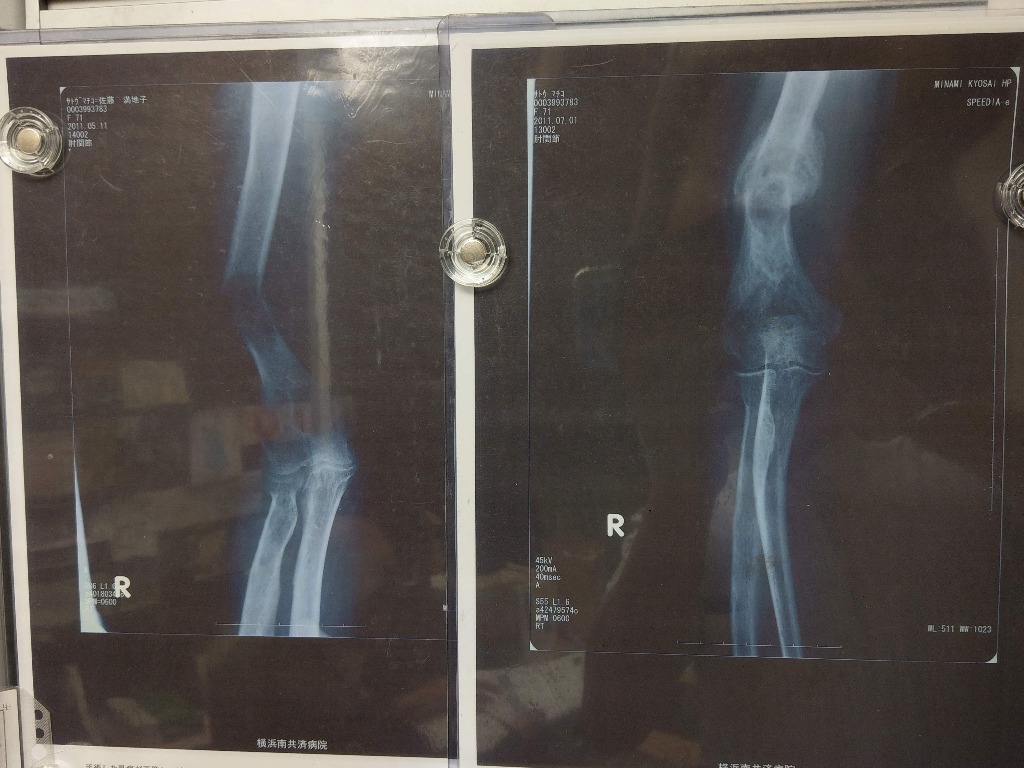

乳がん~骨髄に転移した例です。骨が折れていましたが、孟宗竹をエキスバンブリアンを飲用して改善した実例です。